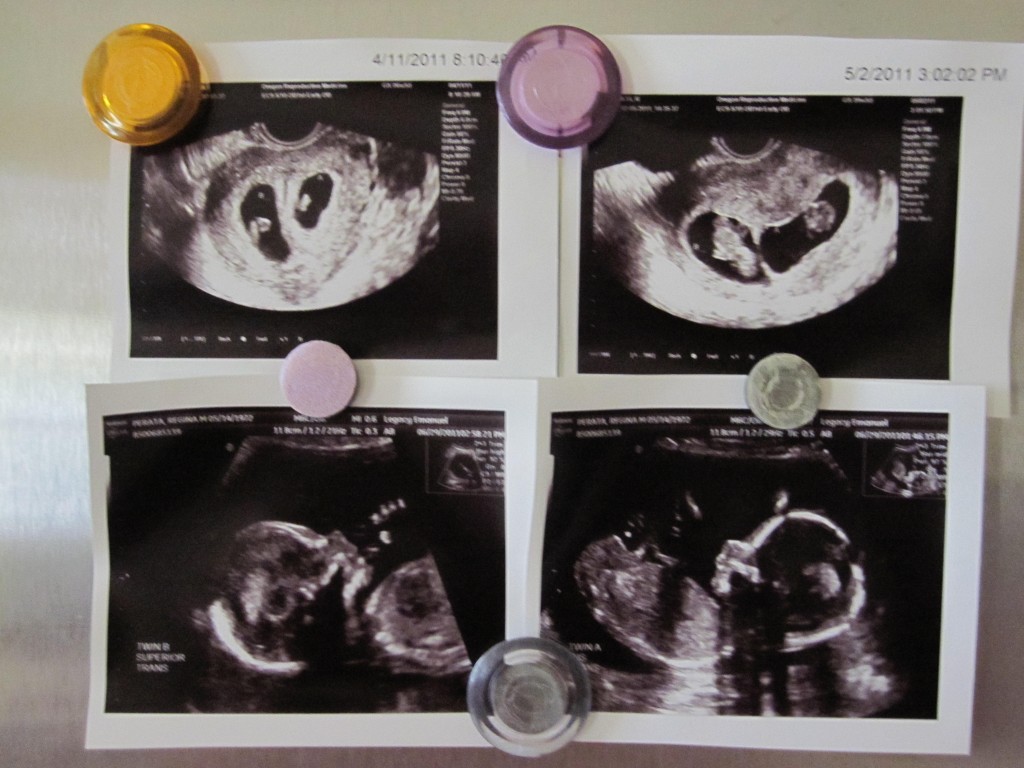

What’s on our Fridge (6wk, 9wk, 18 wk ultrasound pics)